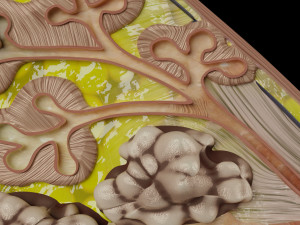

This is a 1:1 scaled model of right breast cut opened in sagittal plane to reveal its internal antomy and histology (schematic). The deeper parts and fascial layers are also depicted to give a very detailed approach to the model. The full layers starting from skin, nipple areola, till intercodtal muscles and ribs are also depicted.

breast mammary gland female chest wall anatomy human medical science reproductive genitalia muscle fascia milk nipple areola subcutaneous fatДо даного товару немає коментарів.